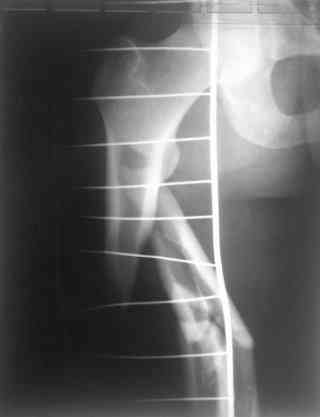

Re: С3-перелом бедра как лечить дальше?....

Dmitry Katritsa 25 Сентябрь 2007, 20:56

одна проблема в моей компьютерной неграмотности(не смог прикрепить снимки), а другая в том, что связь с пациентом потеряна и,насколько я понял в своем регионе ему посоветоваться не с кем, кроме главного врача который отреагировал на выбранную нами тактику так: "там тебя использовали в качестве подопытного кролика...".

Надеюсь сейчас показать перелом, а потом синтез.